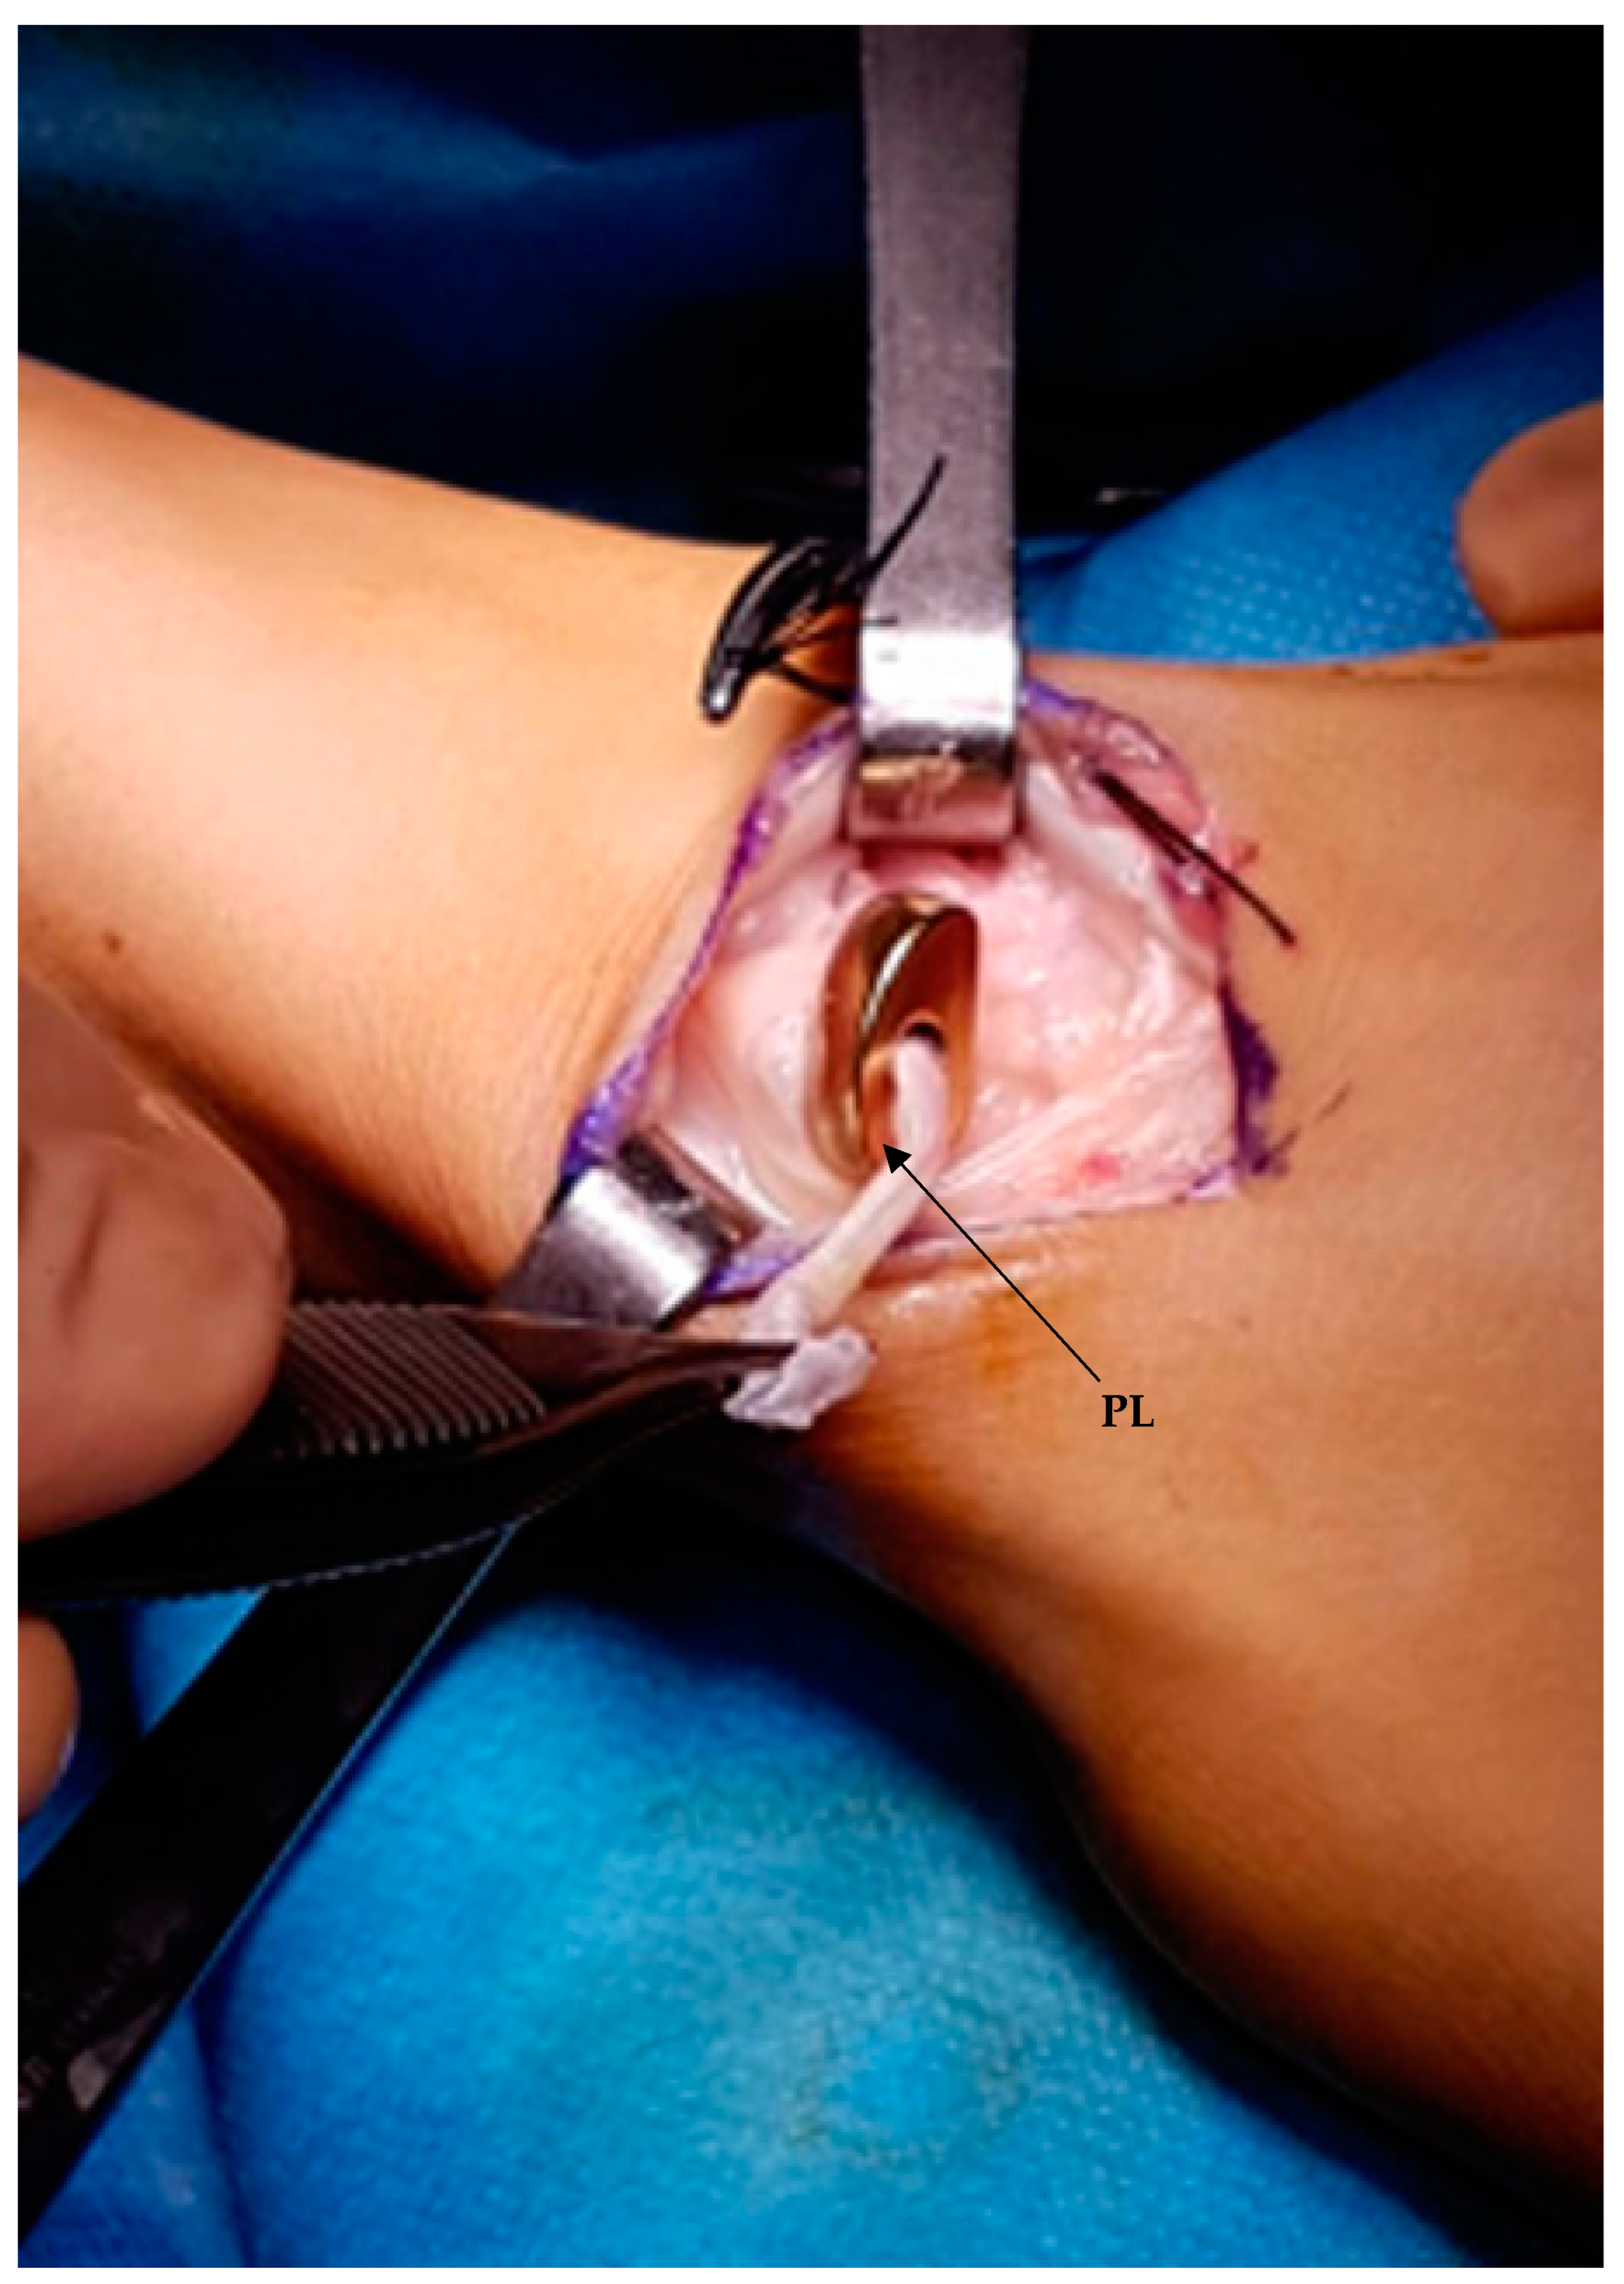

2.4. Surgical Technique